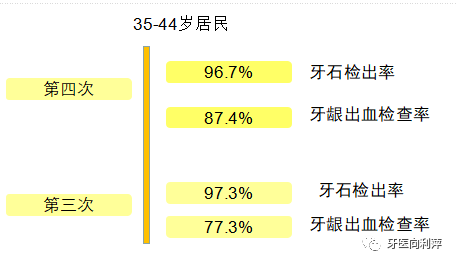

上一期的牙周疾病知识科普中,我们已经了解到何为牙周病以及它有哪些表现。针对此,很多好奇的宝宝们已经发问了,为什么自己每天早晚刷牙还是会染上“牙周炎”这个怪疾呢,牙结石难道不是每个人都有吗?最后这个问题是恰到好处了,来看看去年国家卫计委发布的第四次口腔健康流行病学调查结果,你就会知道为什么说牙周医生任重道远了!